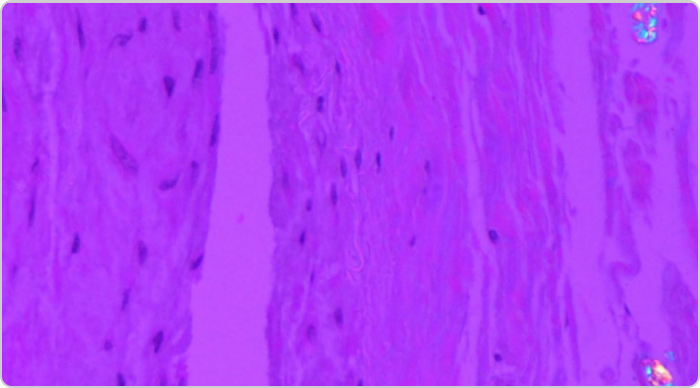

Photo of tophi from gout in spine

(A) lntraoperative photograph of the chalky white material at the right L2-L3, L4-L5 facet joints (white arrows).

(B) Histological examination (H&E, 100x) shows amorphous tophaceous deposit with a multinucleated giant cell reaction.2

Adapted from Lu H, et al. Medicine (Baltimore). 2017;96:e7670.

KRYSTEXXA has not been studied to reverse damage to the spine or any of the body's organs.